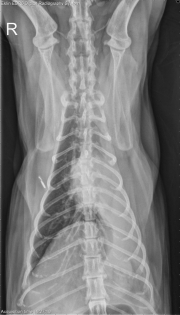

8 year old male neutered Domestic Shorthair with 1 month of anorexia and weight loss. What is the primary problem?

VD Thorax

There is a rounded soft tissue mass superimposed on the heart base on both lateral projections, causing ventral deviation of the carina. On the ventrodorsal and dorsoventral projections, there is a mediastinal shift to the left and atelectasis of the left lung lobes. The right lung lobes are hyperinflated. There is a moderate bronchial pattern throughout the lungs.

• Pulmonary mass causing bronchial obstruction and secondary volume loss in the left lung lobes (neoplasia, abscess, granuloma).

• Pulmonary abscess (Nocardia or Actinomyces)

• The mass was confirmed by ultrasound and a fine needle aspirate was obtained for cytology. No further treatment was pursued.